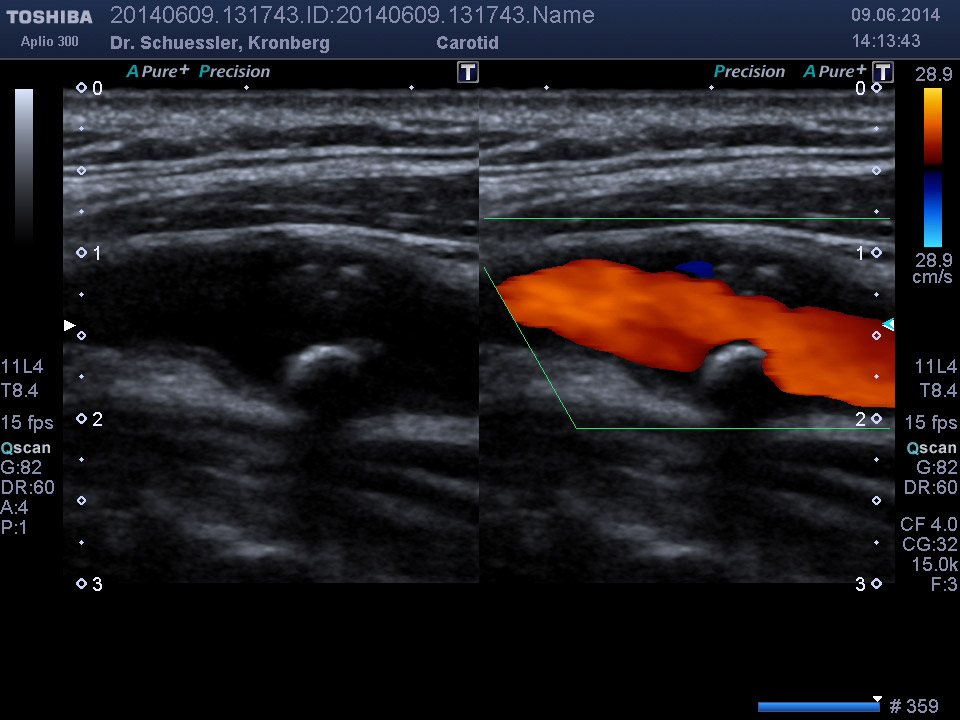

Die farbkodierte Duplexuntersuchung der Gefäße ist ein Ultraschallverfahren und gibt u.a. Auskunft über Verkalkungen, Einengungen, Verschlüsse oder Thrombosen im Bereich der Arterien und Venen.

Sie kann in allen Gefäßregionen des Körpers zur Anwendung kommen.

Die Untersuchung wird angewandt zur Diagnostik von Verengungen in den hirnversorgenden Arterien, Erweiterungen (Aneurysmen) oder Verengungen der Bauchschlagader, Verengungen der Nierenarterien bei Bluthochdruck,  Venenthrombosen und zur Bestimmung des Gefäßrisikoprofils.